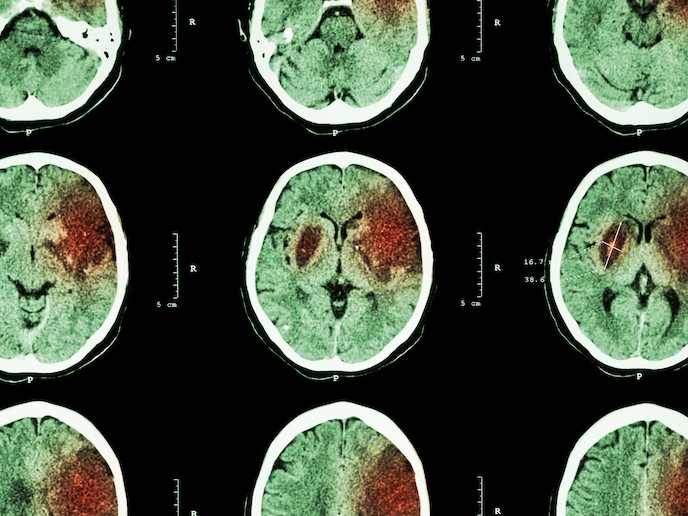

Stroke is caused either by haemorrhage (bleeding due to rupture of blood vessels in the brain) or by a blockage of arteries in the brain. It is estimated to affect 13.7 million people worldwide every year, with 116 million healthy years lost(opens in new window) (Disability-adjusted life years – DALYs) due to death and life-long sensory, motor or cognitive disabilities. Over the last two decades, developments in prevention and treatment have reduced the proportion of people suffering from a stroke, while recovery has also significantly improved. Despite this, with an increase in the number of over 70-year-olds, the absolute number of strokes is due to increase. With one report anticipating an increase of 34 % in stroke incidents between 2015 and 2035(opens in new window), prevention and treatment are fast becoming high clinical priorities. Within the first hours after a stroke, patients can be treated with recanalisation therapies, such as thrombolysis(opens in new window), but globally only a minority of patients actually receive this treatment(opens in new window). Later, during stroke recovery, patients may also receive rehabilitation therapies but these are often insufficient and result in limited effect. There are currently no medical treatments available on the market to support rehabilitation. With EU support, under the SINSTRO project, Sinntaxis(opens in new window) plan to repurpose the drug SIN020 for stroke recovery. As it was previously under clinical development for another illness, it can be entered straight into a Phase II clinical trial.